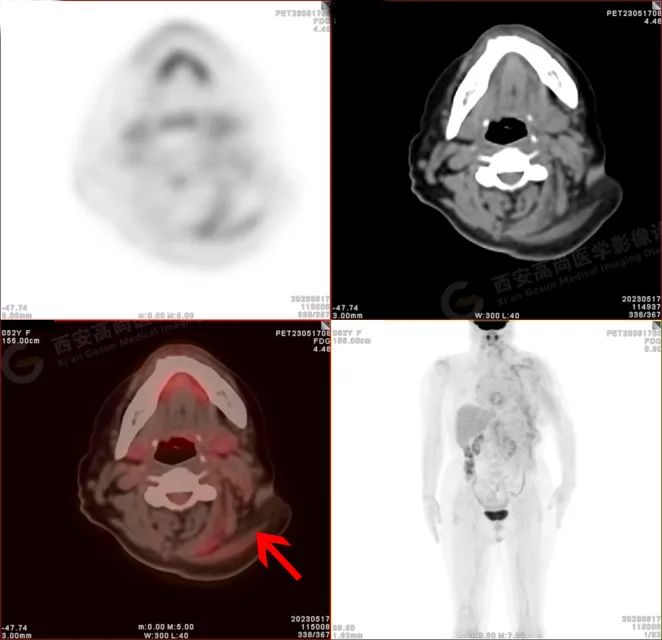

PET/CT 影像图

检查所见

左侧上臂、颈 4-腰 4 椎体水平左侧颈、左侧肩部、左侧腋窝、左侧胸部(含左侧乳腺)、左侧腹部、左侧背部广泛区域皮下及肌肉区可见疏松、肿胀混杂密度软组织病变,边界模糊不清,相邻骨质结构完整,上述病变呈不均匀放射性摄取轻度异常增高,SUV 最大值介于 1.2-2.4。上述改变,符合韧带样纤维瘤病。